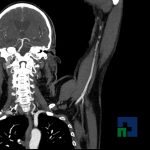

Examinare de rutină cerebrală, nativ și cu substanță de contrast (SDC) pentru diagnosticul:

În cazul traumatismelor cranio-cerebrale:

- Diagnosticul traumatismelor de bază de craniu

- Diagnosticul fracturilor:

- Unice

- Multiple

- Cu înfundare

- Complexe cranio-sinusale

- Complexe cranio-etmoidale

- Complexe cranio-orbitare

- Complexe cranio-faciale